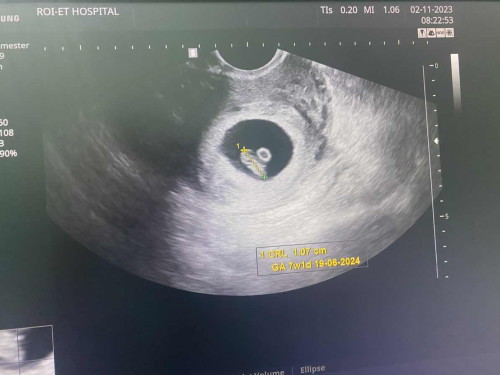

สรุปอายุครรภ์ ยึดตามหมอหรือในแอปคะ

ในแอปคำนวณจากวันแรกของ ปจด ครั้งล่าสุด แต่ไปหาหมอ หมอยึดตามเครื่องซาวด์

ตอนไปฝากครรภ์คุณหมอถามวันสุดท้ายที่มีประจำเดือน แล้วก็ซาวด์ดูเค้าก็บอกว่าขนาดตัวลูกกับอายุครรภ์ก็อยู่ที่ประมาณวันประจำเดือนหมดก็ตรงนะคะ ในแอปก็คำนวณเหมือนที่คำนวณเหมือนที่หมอคำนวณให้เลยค่ะ เพิ่งรู้ว่ามีแบบยึดตามเครื่องซาวด์ด้วยค่ะเพราะส่วนตัวกับคุณหมอก็ยึดตามที่คำนวณค่ะ😅